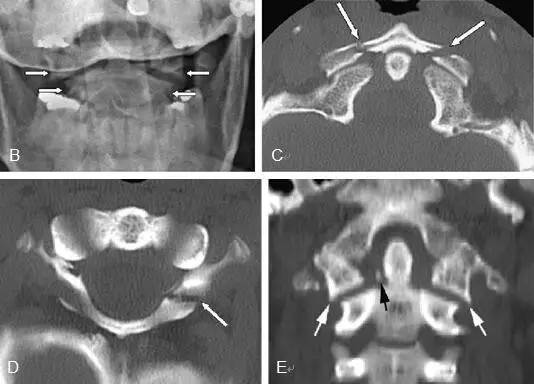

另外一例

Jefferson骨折。A,侧位片示C1后弓骨折线(箭)。B,开口位示C1侧块相对于C2偏移(箭)。C和D,轴位CT图像示骨折线通过C1环前、后部(箭)。E,冠状位CT图像示翼状韧带小的撕脱骨折(黑箭)。此图像上也标注了C1在C2上方偏移(白箭)。